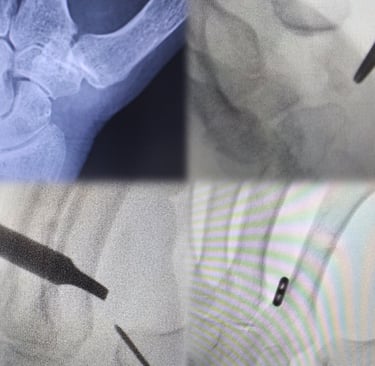

A través de pequeñas incisiones y bajo visualización artroscópica, se reseca únicamente la porción patológica del trapecio, conservando la estabilidad y la biomecánica del pulgar. Esta técnica permite un menor dolor postoperatorio, movilización precoz y una recuperación funcional más rápida en comparación con técnicas abiertas más agresivas.

La artrodesis trapeciometacarpiana por artroscopia permite tratar la rizartrosis avanzada mediante la fusión controlada de la articulación, preservando la biomecánica del pulgar y reduciendo el dolor de forma definitiva. La asistencia artroscópica facilita una preparación precisa de las superficies articulares y una mínima agresión tisular, mientras que los tornillos canulados cruzados aportan una fijación sólida y fiable.